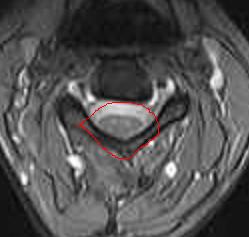

Il fenomemo descritto nell’articolo precedente si chiama “cord Thetering” che significa proprio stiramento midollare.

Praticamente questo meccanismo provoca una compressione sul midollo senza che si sia un’ernia discale a spingere! La compressione non è su una radice, ma sul midollo stesso.